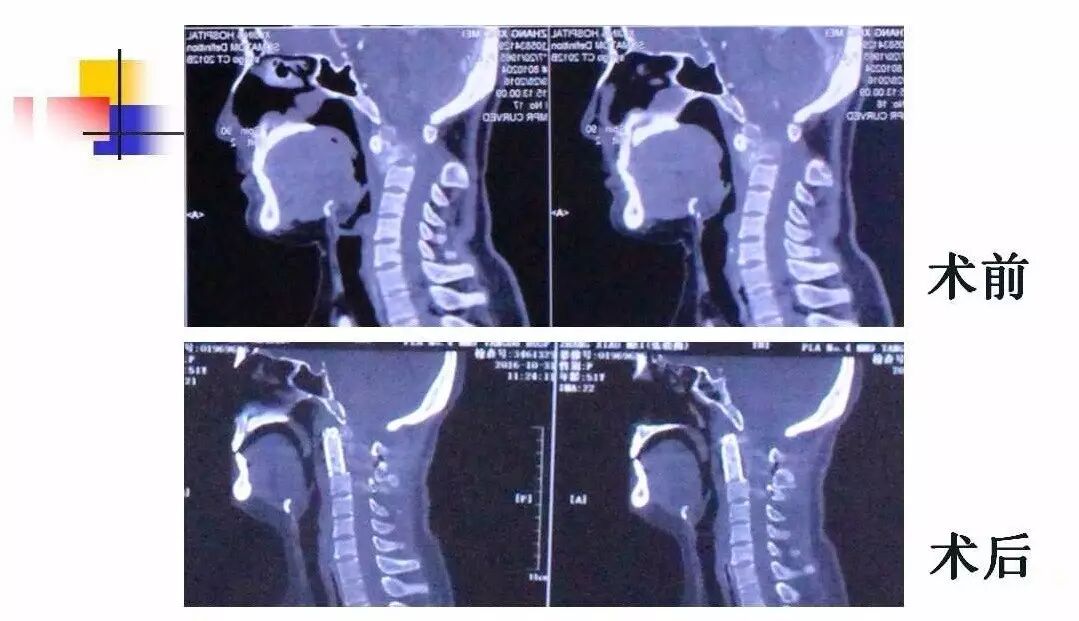

在脊柱神经外科、显微神经外科和颅底肿瘤外科前沿研究和临床诊治领域有着扎实的基础,为全国首批获得脊柱神经外科医师培训认证的神经外科医生。擅长颈椎病、椎管肿瘤及各种脊柱疑难疾病的诊治、脑肿瘤微创手术,尤其擅长颈椎退行性疾病的手术,率先在国内开展了颅底凹陷后路复位、颈前路减压融合等高难度手术,多年来收治了来自全国各地的大量患者,疗效达到国内领先水平。